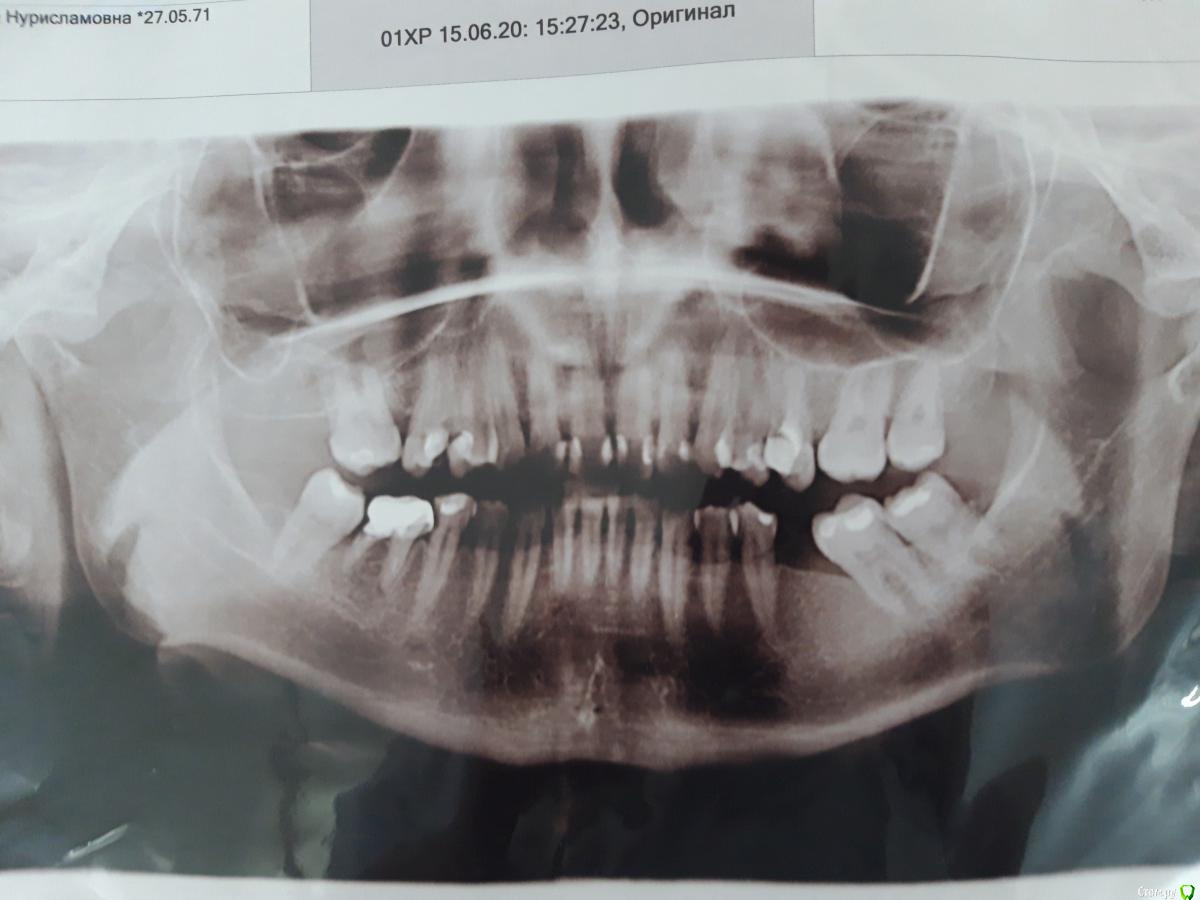

DemidovaLuda Опубликовано 16 июня, 2020 Автор Поделиться Опубликовано 16 июня, 2020 а конкретнее? Здравствуйте, в области верхушек 34-го и 35-го зубов, обширная деструкция костной ткани без четких границ. Подскажите, что это может быть? Ссылка на комментарий

red_butler Опубликовано 16 июня, 2020 Поделиться Опубликовано 16 июня, 2020 Здравствуйте, в области верхушек 34-го и 35-го зубов, обширная деструкция костной ткани без четких границ. Подскажите, что это может быть?Качество снимка не позволяет дать ответ, но предположу что 3.5 3.4 интактные, то есть здоровые... заберите в клинике снимок в электронном виде и перезалейте его 3 Ссылка на комментарий